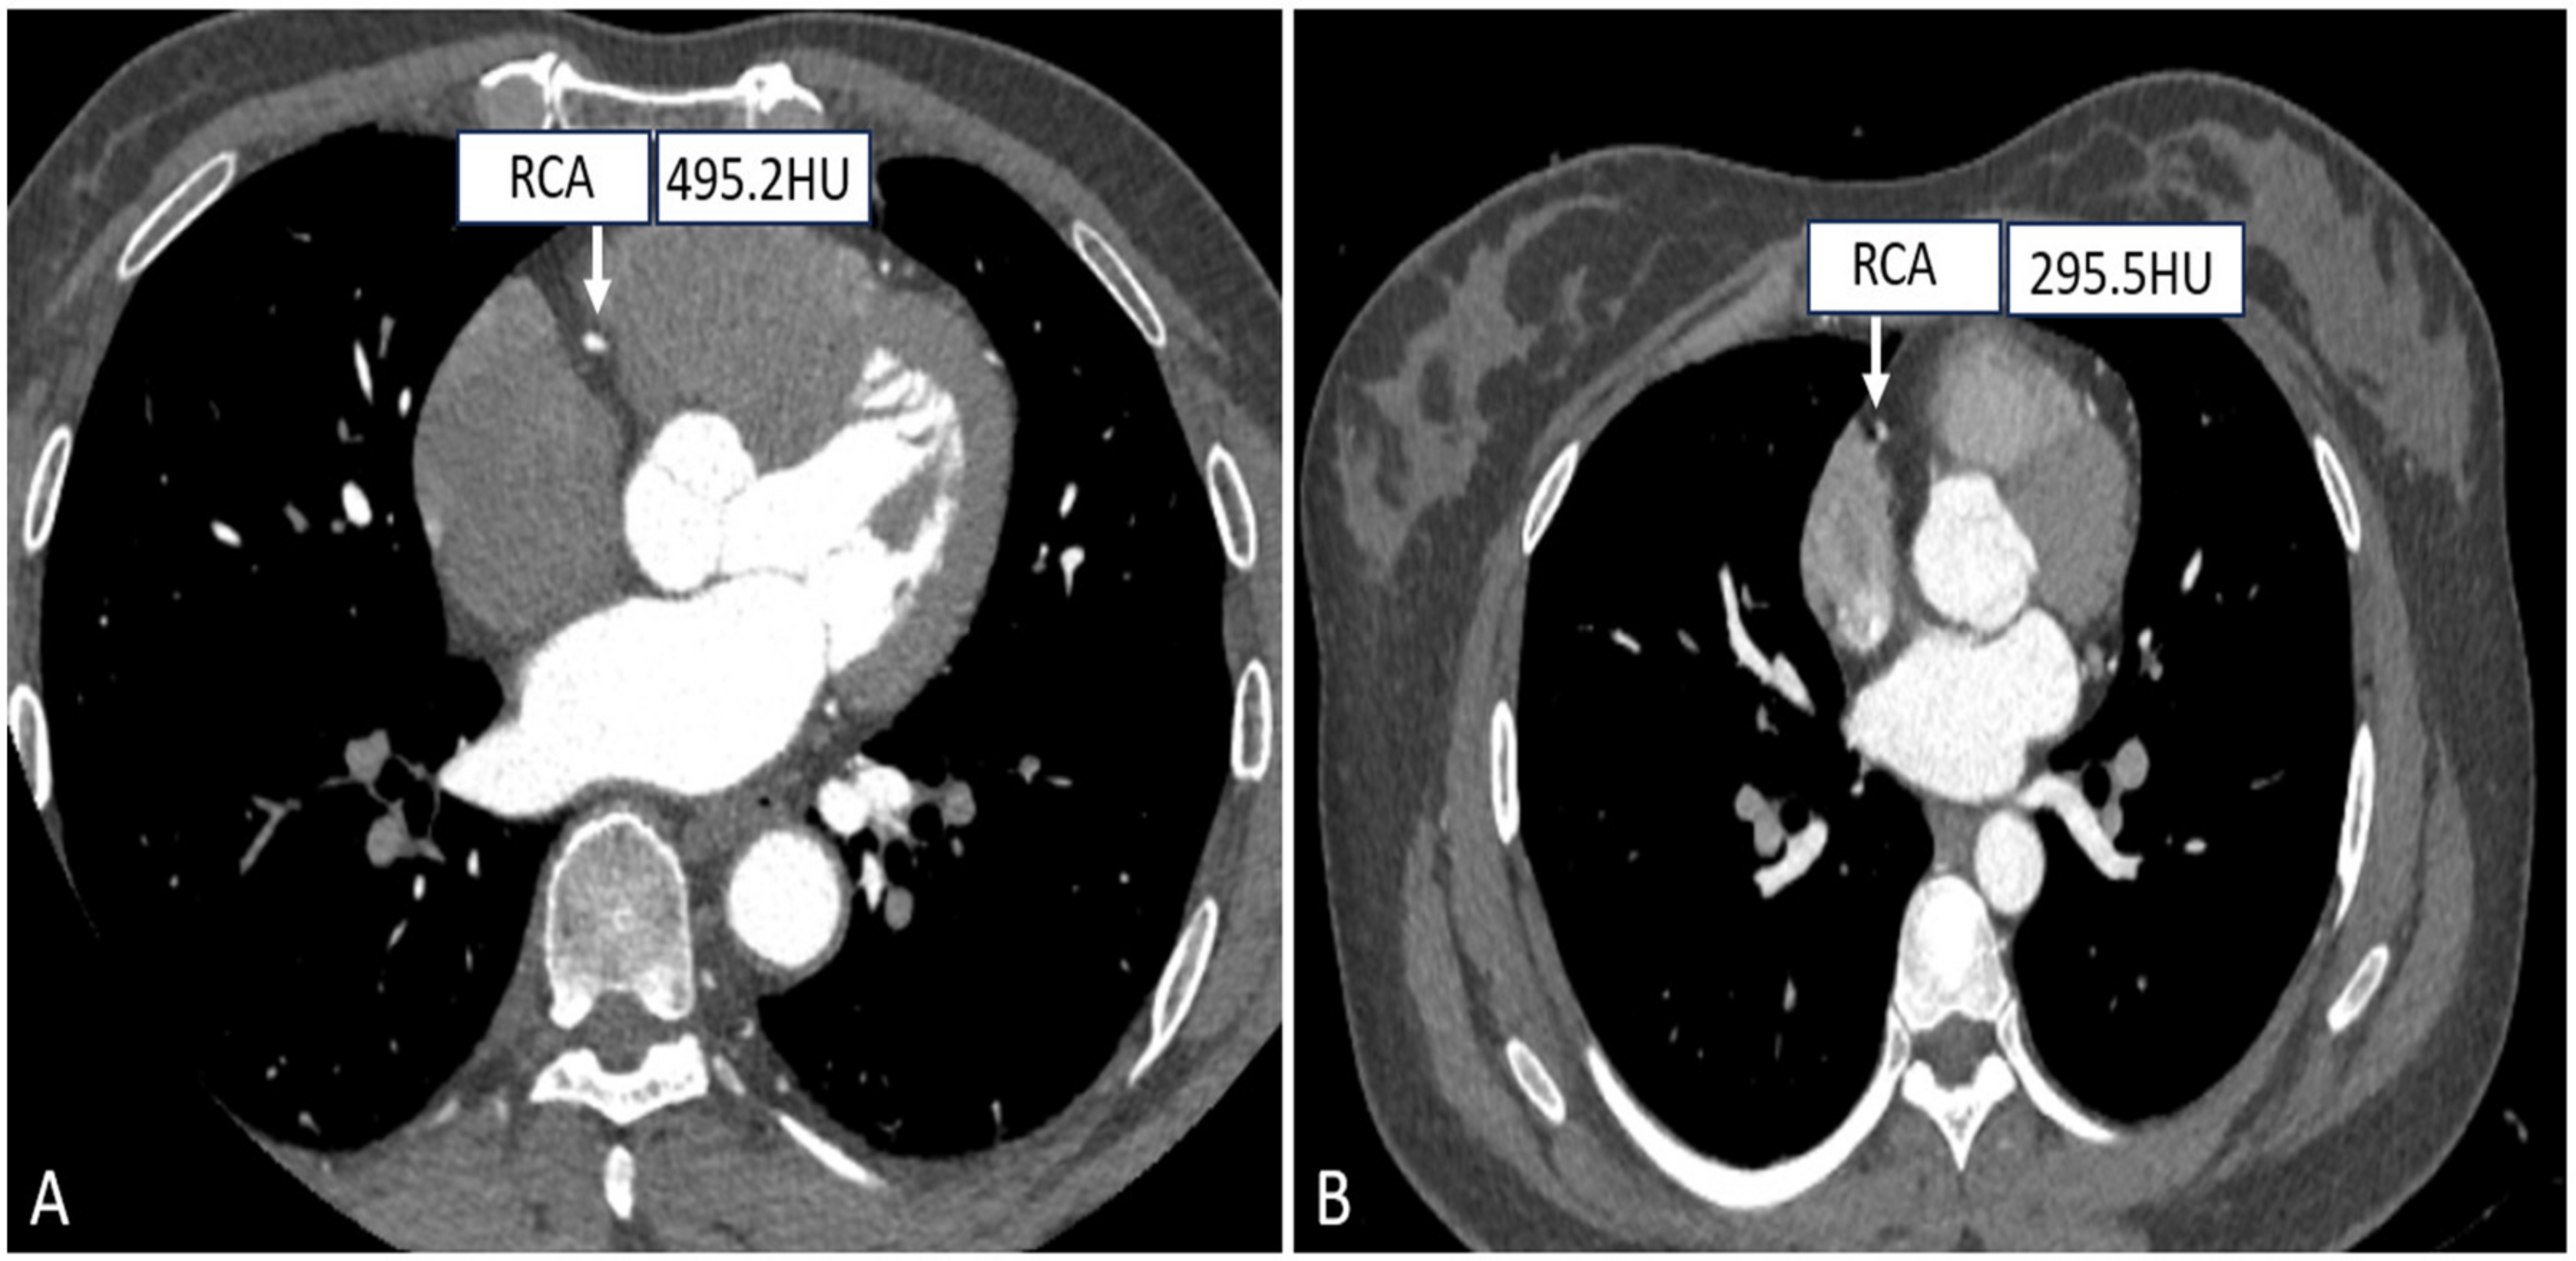

- Muenzel, D.; Noel, P.B.; Dorn, F.; Dobritz, M.; Rummeny, E.J.; Huber, A. Coronary CT angiography in step-and-shoot technique with 256-slice CT: Impact of the field of view on image quality, craniocaudal coverage, and radiation exposure. Eur. J. Radiol. 2012, 81, 1562–1568. [Google Scholar] [CrossRef]